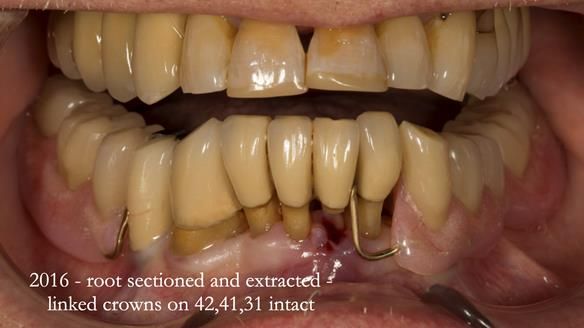

In 2016, Ken developed pain from tooth 32.

Endodontics was not possible.

The root was resected.

The tooth was already linked to 41 and 42,

and we were able to retain it

without compromising denture stability or retention.